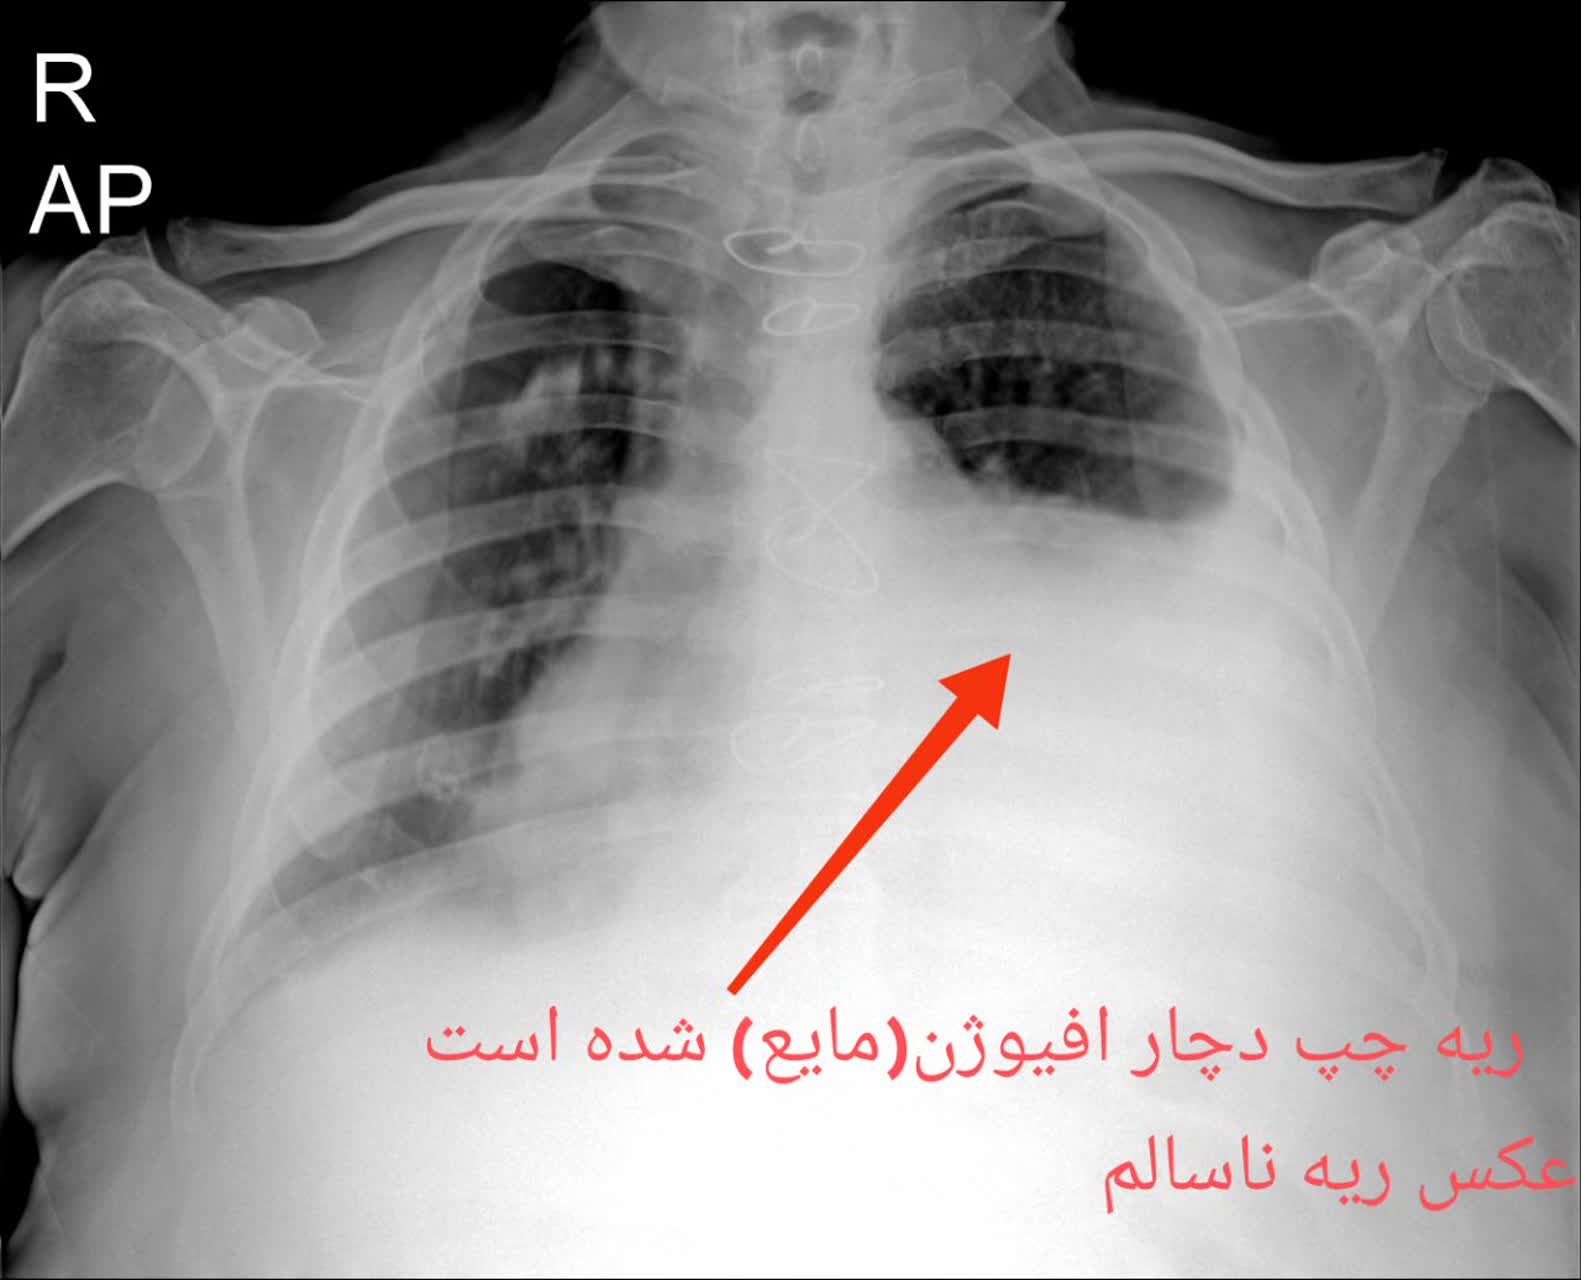

مقایسه عکس ریه سالم و ناسالم

در عکس ریه سالم و ناسالم، تفاوتها معمولاً با چشم غیرمسلح نیز مشهودند. ریه سالم تصویری یکنواخت و شفاف دارد، با خطوط ریوی طبیعی و بدون سایه یا توده. در مقابل، ریه ناسالم ممکن است سایههای غیرطبیعی، نواحی سفید شده (indicative of consolidation)، خطوط پررنگتر ناشی از فیبروز یا تودههای نامنظم را نمایش دهد. تشخیص این تفاوتها توسط پزشک رادیولوژیست، نیاز به تجربه و تجهیزات باکیفیت دارد، چیزی که در خدمات رادیولوژی ریه در منزل تهران و رادیولوژی ریه در منزل کرج فراهم شده است.